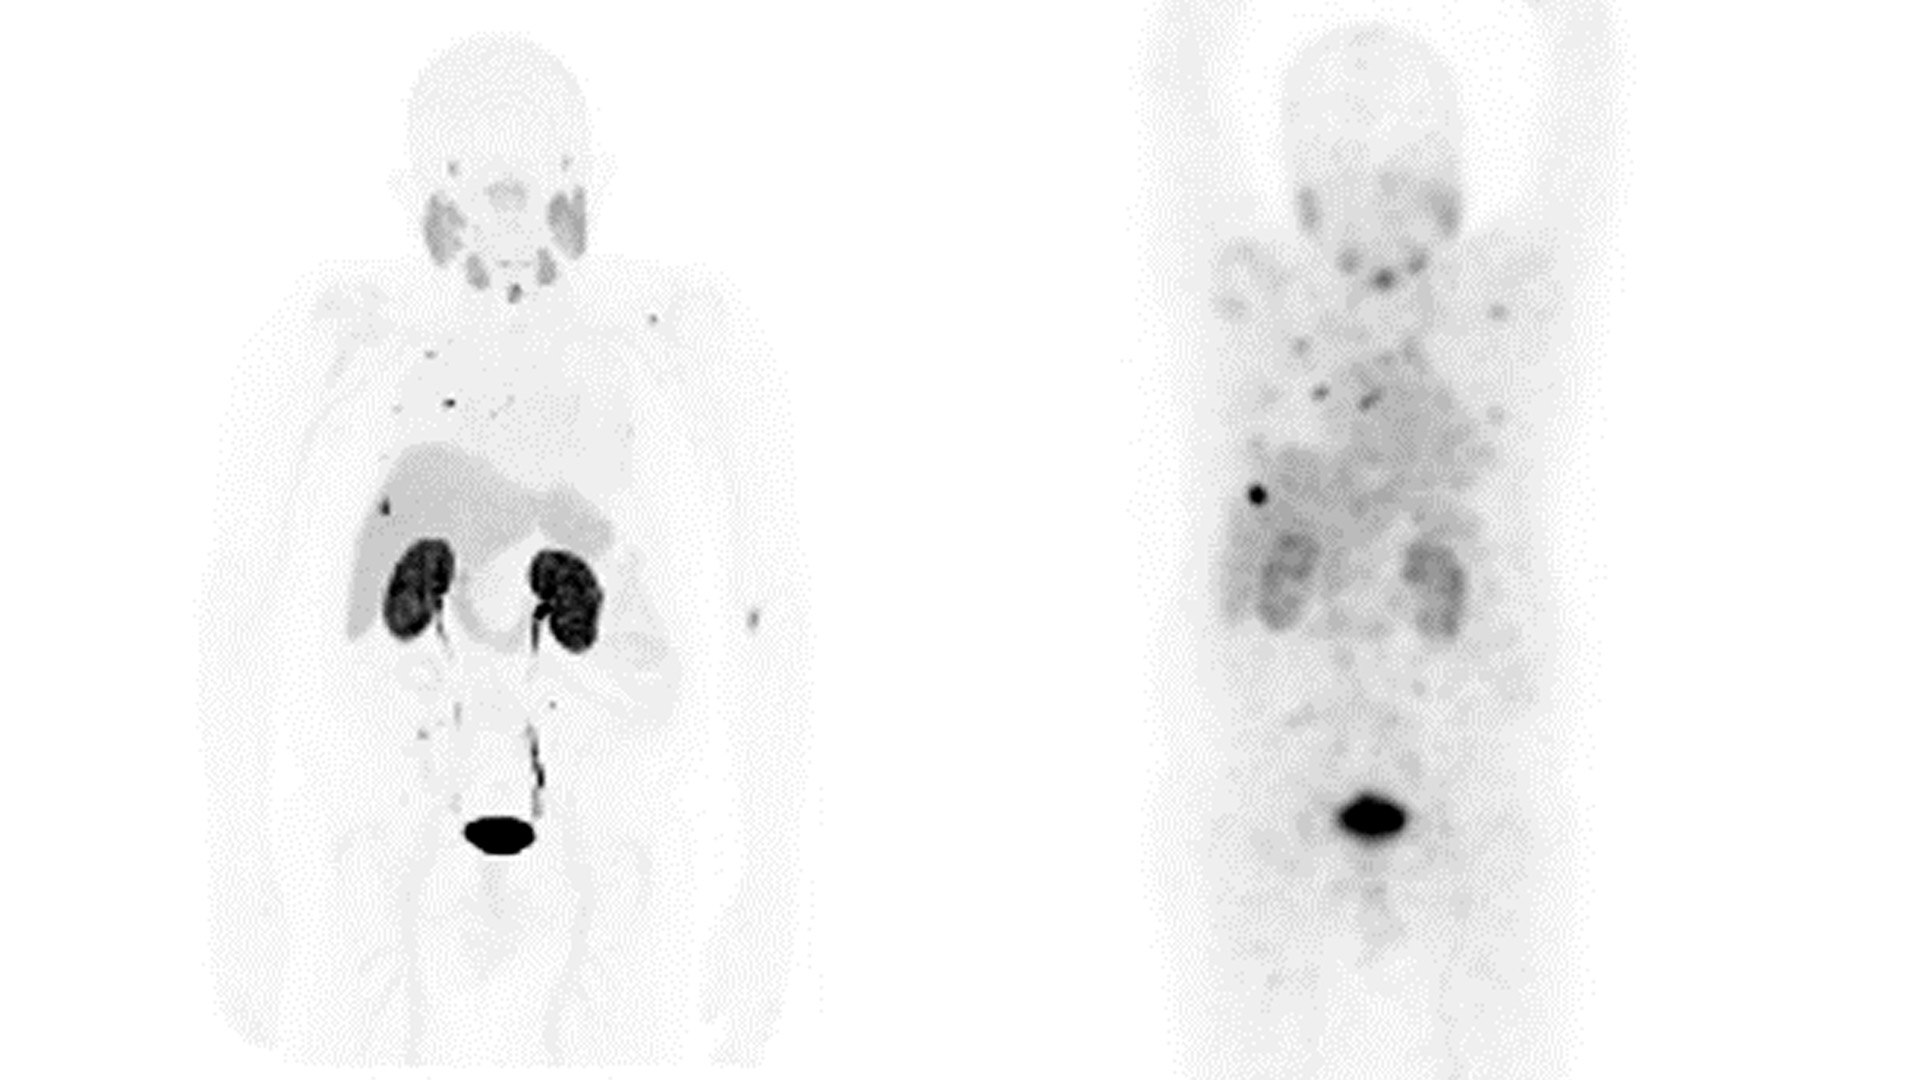

DIAGNÓSTICO

GE HealthCare es pionera en soluciones que permiten una sensibilidad y una confianza en el diagnóstico sin precedentes.

Nuestra exclusiva gama de soluciones de adquisición de imágenes para diagnóstico centradas en la Teranóstica se ha diseñado específicamente para satisfacer las necesidades de los médicos y de sus pacientes, hoy y en el futuro.

ADQUISICIÓN DE IMÁGENES Y MONITORIZACIÓN DEL TRATAMIENTO

GE HealthCare está dando forma hoy al futuro de la Teranóstica con soluciones precisas de adquisición de imágenes y monitorización, así como con innovaciones en la respuesta al tratamiento.